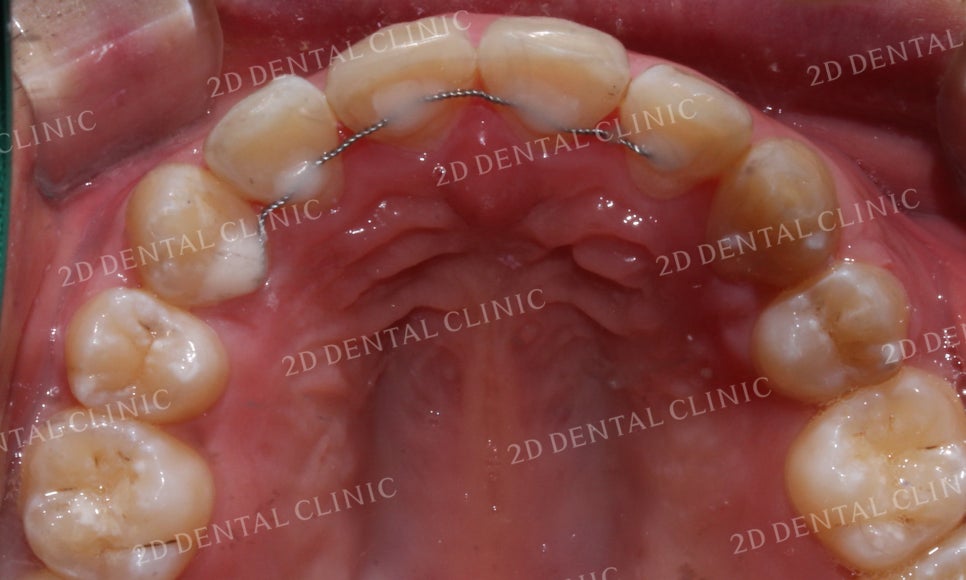

<Before> <After>

상악의 설측면을 보시면

중절치가 전방으로 뻐드러져

있었던 교정 전 모습에서

교정 후 중절치의 뻐드러짐 없이

고르게 바뀐 모습입니다.

또한 V-Shape으로 좁게 모여있던

악궁이 교정 후 U자 형태로 자연스럽게

확장된 모습입니다.